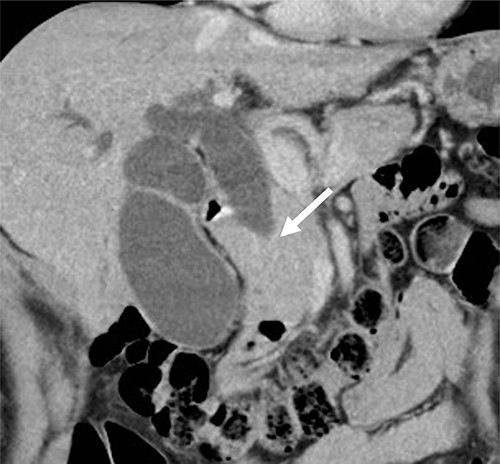

Contrast-enhanced computed tomography (CT) revealed wall thickening and stricture of the distal common bile duct (CBD) (Fig. 1). Dilation of both the intrahepatic bile ducts and the common hepatic duct was also observed (Fig. 2). No lymph node or distant metastases were observed. Endoscopic retrograde cholangiopancreatography revealed irregular stenosis in the distal CBD (Fig. 3). Thereafter, biliary drainage and brush cytology were performed, and an adenocarcinoma was detected.

CT scan showed wall thickness and stenosis of the distal CBD (arrow).